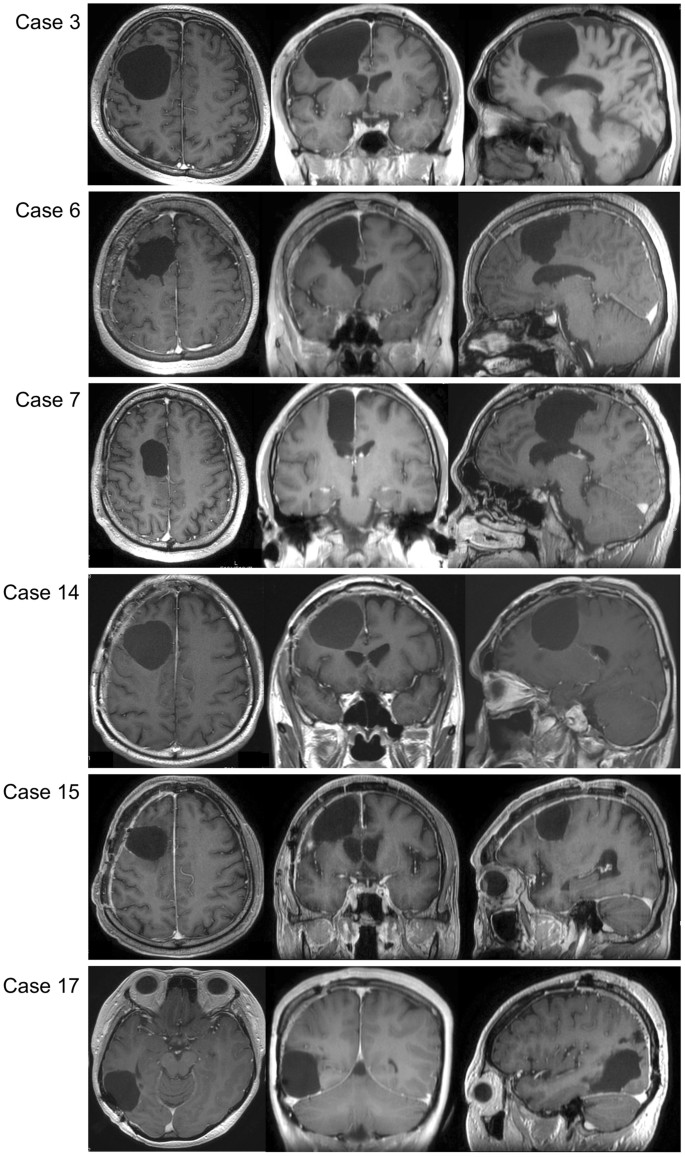

To investigate surgical influences, we have focused visuospatial cognition in current our research, since the postoperative remaining rate was the highest despite normal preoperative function. In patients with remaining deficits, magnetic resonance (MR) images showed resection of the middle frontal gyrus and/or the dorsal and medial superior frontal gyrus, for five out of six patients (Fig. 5). The voxel-based lesion-symptom (VLSM) analysis was performed to evaluate the anatomical correlates of visuospatial cognitive accuracies and specific association areas. We used as a variable the average of the absolute value of the amount of deviation. Figure 6 shows the statistical map from the VLSM analysis performed on the line bisection test. The largest cluster of significant voxels was located in the deep region of the medial superior frontal gyrus and middle frontal gyrus (Z max = 2.83; p < 0.05, FDR corrected). Following this, the VOI of significant voxels was overlaid with the VOIs for the SLFs I and II on the MNI template (Fig. 6, lower column). The result showed that the statistically significant clusters from the VLSM analysis (p < 0.05) were located on the middle of the SLFs I and II and the external side of the SLF II (the VLSM analyses for other functions, see Supplementary Figure 1). In postoperative neuropsychological examination, degree of abnormal deviations of line bisection test at postoperative 3 months were 7–13 mm left-ward deviation in 5 cases (Cases 6, 7, 14, 15 and 17) and 7–14 mm right-ward deviation in 1 case (Case 3). Unfortunately, these 6 patients complained related to visuospatial cognitive deficit in their social lives, even after they returned to their work. Though these patients could easily perform self care activities, their deficit influenced on the activity which needed high attention, such as driving or office job. Their deficit lasted more than 1 year after surgery. Importantly, as for these patients with frontal lesion, they could not perform the line bisection test during awake surgery, because of movement disorders of upper limb induced by intraoperative SMA syndrome16. Consequently, we failed to assess visuospatial cognition accurately in 5 patients with frontal lesion. In contrast, in patients whose visuospatial cognition could be assessed and preserved during awake surgery, their postoperative visuospatial cognition was successfully preserved, except Case 17. Two illustrative cases are shown in Fig. 7. The positive mapping site of subcortical region is located on the course of the SLF II. Additionally, in patients who showed deficit and recovery, deep parts of the superior frontal gyrus and middle frontal gyrus were preserved except in Cases 5 and 16 (Supplementary Figure 2).

Postoperative MR images of patients whose visuospatial cognitive lasted ≥3 months. In the left, middle and right columns, T1 weighted MR images of axial, coronal, and sagittal slices, respectively, are shown for each patient. Resection cavities are in the middle frontal gyrus and/or superior frontal gyrus including the medial region in patients with frontal lesion.